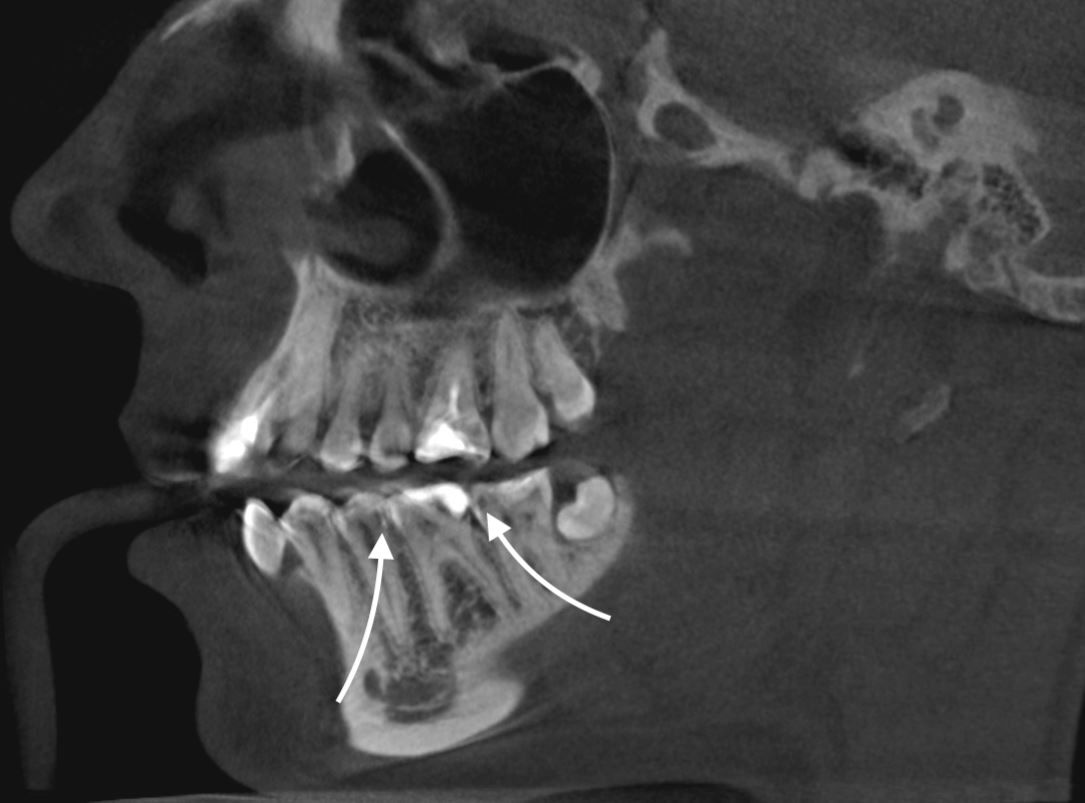

Стрелками указан "контаткный кариес" на зубах 3.5, 3.7